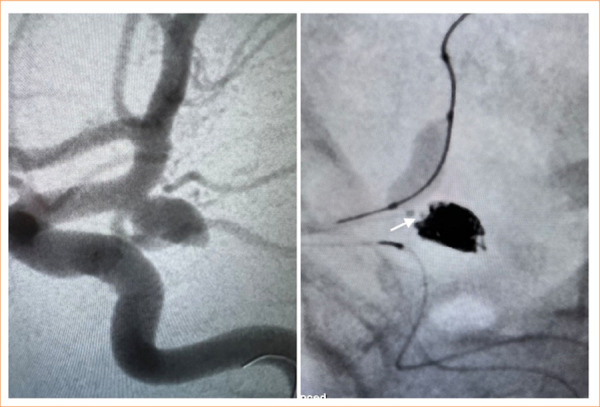

Purpose: To evaluate the angiographic outcomes of the Optima™ coil system in the endovascular treatment of saccular intracranial aneurysms to present real-world experiences.

Methods: The study encompassed patients with both ruptured and unruptured aneurysms who underwent treatment with the Optima™ coil system. A retrospective analysis was conducted to examine patient and aneurysm characteristics, complication rates, and angiographic outcomes.

Results: The total of 326 Optima™ coil implantations was performed in 64 aneurysms, with a mean maximum diameter of 7.49 ± 3.08 mm (range: 2.5-16.5 mm), among 64 patients (37 females and 27 males, mean age: 53.34 ± 14 years old). The average number of implanted coils was 5.06 ± 1.73. The mean packing density was 26.2% (range = 19.2-34.6), observed to be significantly higher in aneurysms with complete occlusion and neck remnants compared to those with a residual dome (p < 0.01). The mean follow-up period was 15.9 ± 8.1 months. One case (1.5%) reported a coil malfunction attributed to coil stretching. The mortality rate was 3.1% (n = 2).

Conclusion: The Optima™ coil system exhibited safety and efficacy in the endovascular treatment of both ruptured and unruptured intracranial aneurysms, demonstrating favorable angiographic outcomes. Nevertheless, further studies are necessary to validate these results over the long term.